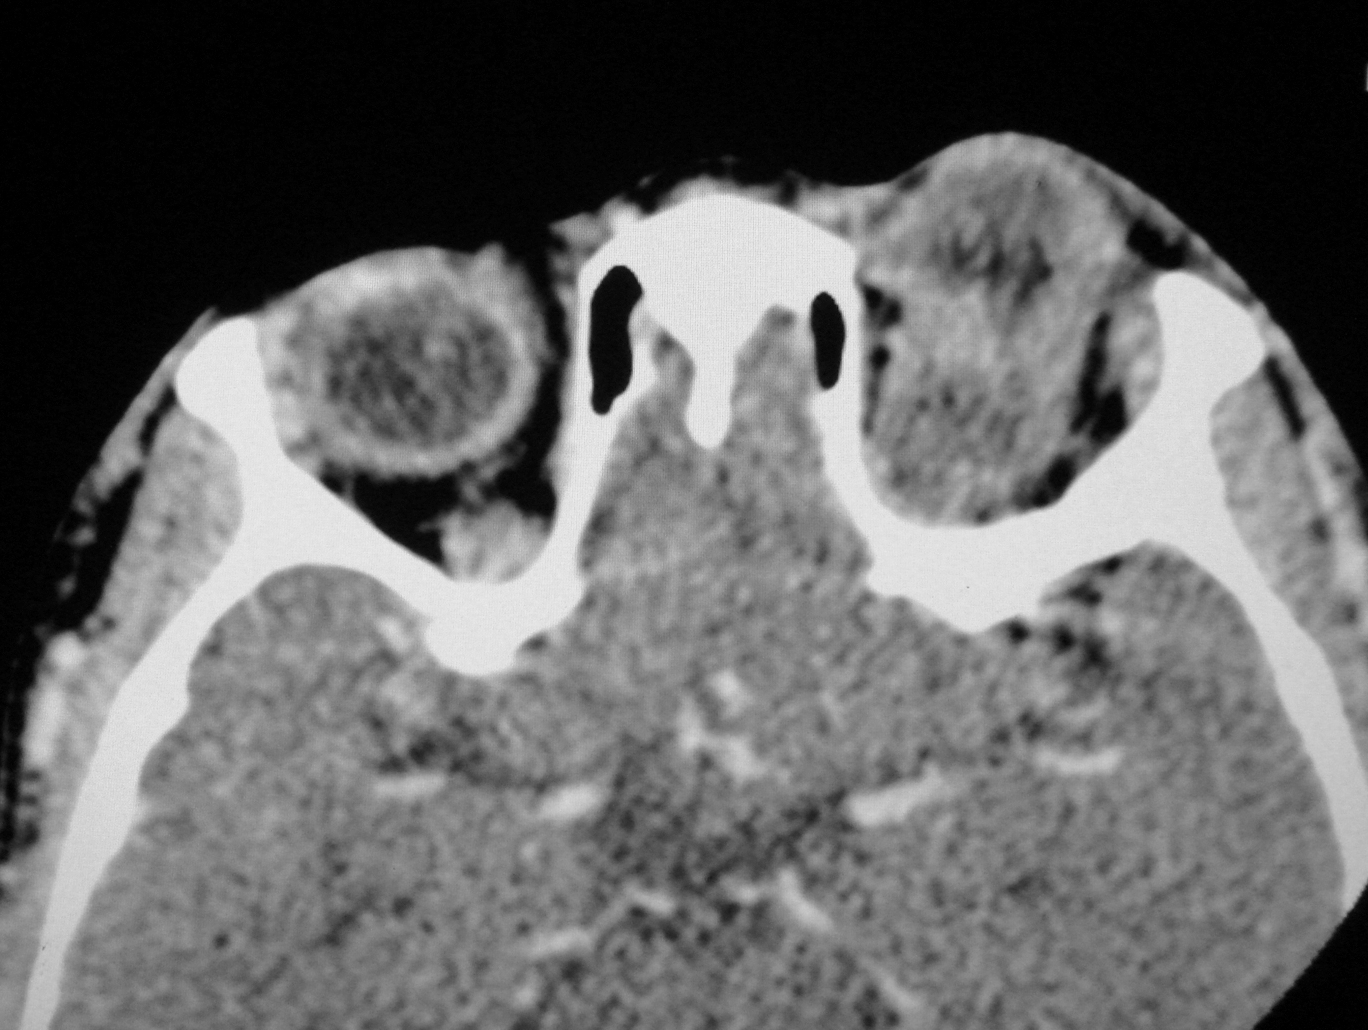

The ocular involvement of the cysticercosis is a rare entity involving eyelids, extraocular muscles, orbit, conjunctiva, anterior chamber, uvea, retina, vitreous and optic nerve. All the extraocular muscles are involved in myocysticercosis. Ultrasonography and Computed tomography are the imaging modalities for evaluation of ocular cysticercosis. The patients can be treated with systemic steroids and albendazole; however surgical excision is the treatment of choice. We report a rare case of extraocular myocysticercosis in nine years old boy diagnosed on ultrasonography and computed tomography.